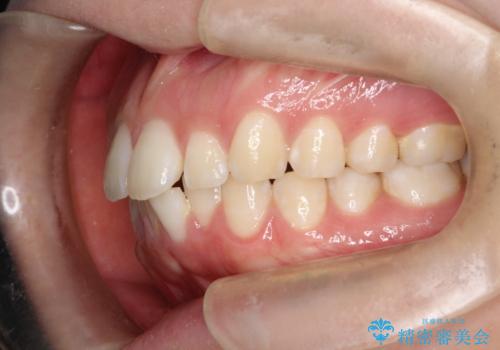

- 横から見たときの口元が出てるの気になるとのことで来院されました。

口元の突出感と口唇の閉じずらさが確認されました。

上下左右の歯を1本ずつ、合計4本抜歯しして前歯を後方に下げて、口元の突出感を改善する計画としました。